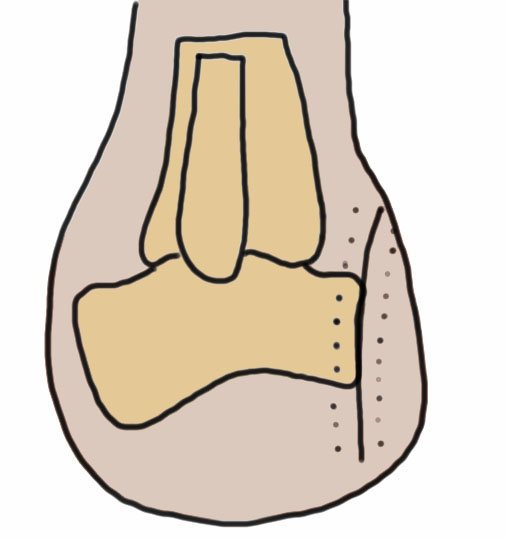

Chopart Amputation

Midtarsal amputation

Modified Chopart: tendon balancing

Technique

- preserve talus and calcaneus

- avoid equinus and varus

- fish mouth incision

- divide talonavicular and calcaneocuboid joint

- Z lengthen achilles tendon

- reattach tibialis anterior to neck of talus

- reattach tibialis posterior to talus

- reattach peroneus brevis to calcaneus